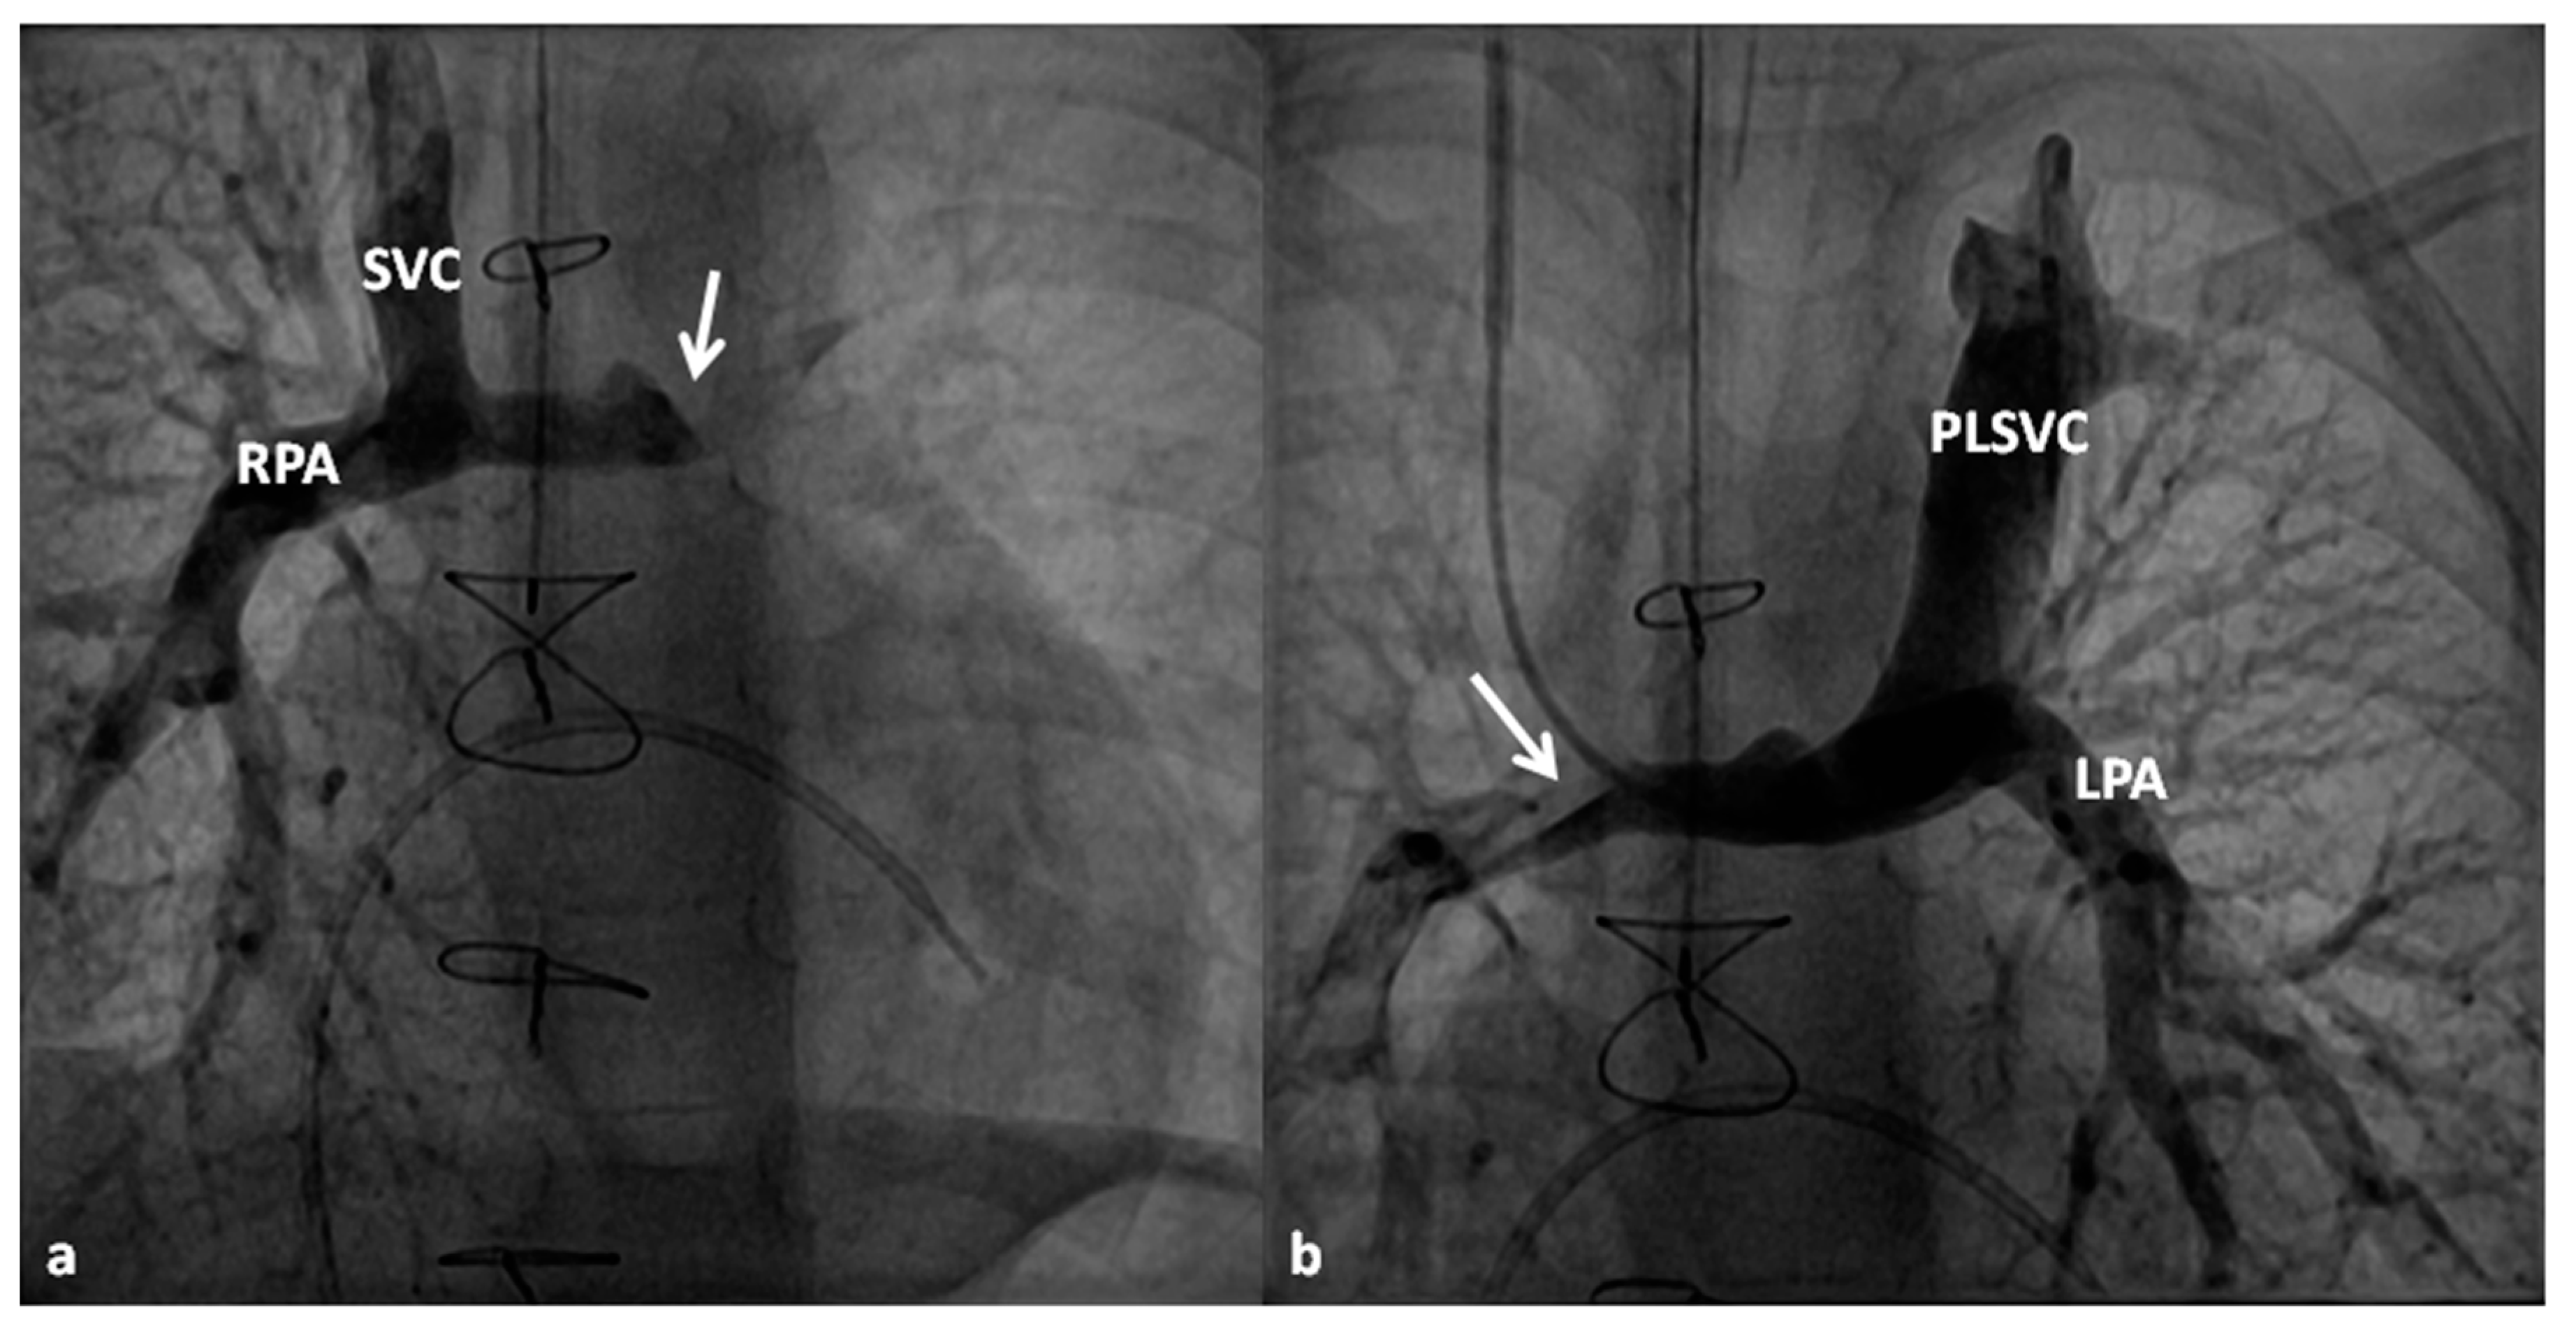

4.2.3. Stage IIIA

Between the ages of one and four years, usually one year after the bidirectional Glenn, Fontan completion is performed by redirecting the inferior vena caval flow into the PA by either a lateral tunnel [81] or an extra-cardiac non-valved conduit [76]. Extra-cardiac conduit with fenestration (Figure 10) is preferred by most surgeons. Cardiac catheterization and selective cine-angiography is usually performed prior to this surgery to evaluate pulmonary artery anatomy and pressures, trans-pulmonary gradient, pulmonary vascular resistance (PVR), and LV end-diastolic pressure to ensure their normalcy prior to proceeding with Fontan completion. Some centers use magnetic resonance imaging (MRI) for evaluation instead of angiography. During this catheterization, significant collateral vessels, if present, are trans-catheter occluded by most cardiologists.

4.2.4. Stage IIIB

The fenestration is closed by trans-catheter device implantation (Figure 11) six months to one year after stage IIIA. Occlusion of the fenestration is not necessary in all patients, although the author recommends closure to prevent arterial desaturation and paradoxical embolism.